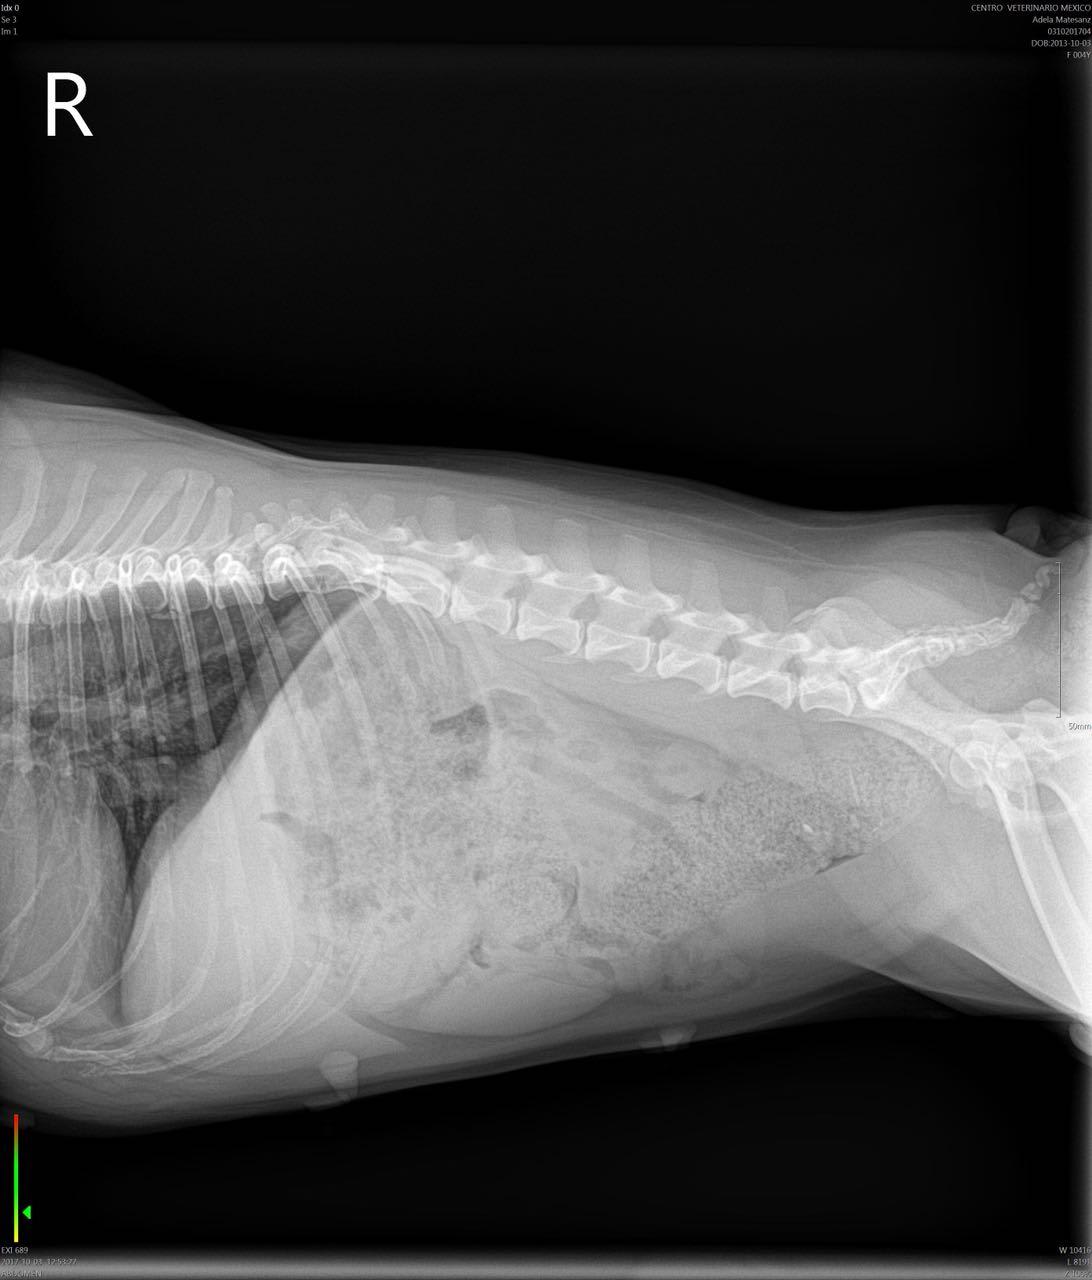

Hello, my dog was chewing on a pork rib bone yesterday and i think i got most of it out, she's a 4 year old french bulldog not spayed, i gave her a slice of bread right after soaked in olive oil and she puked it, took her to the vet they got xrays she was hacking and coughing this morning the xrays dont show a blockage but she ate today and puked all her food and part of yesterdays i checked there were no bones or anything solid in the vomit, she has also been pooping fine